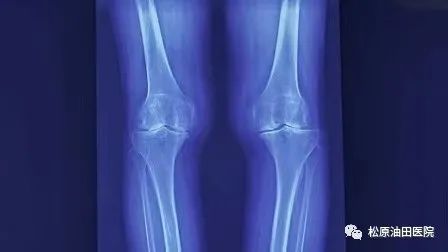

据了解,膝关节骨性关节炎是一种严重影响患者生活质量的关节退行性疾病,其发生率逐年增加,随着我国老龄化的到来,该病已成为第四大致残性疾病,中老年人群多发,且多为女性患者。影像学上表现关节间隙狭窄,关节边缘形成骨赘,其临床表现主要为过度劳累及长期行走时膝关节内测疼痛,休息后疼痛症状缓解,部分患者膝关节肿胀积液,累计内侧间室逐渐发展成为膝关节内翻畸形,常常导致严重疼痛及功能障碍,严重影响患者的生活质量,给患者、家庭和社会造成了沉重的负担。